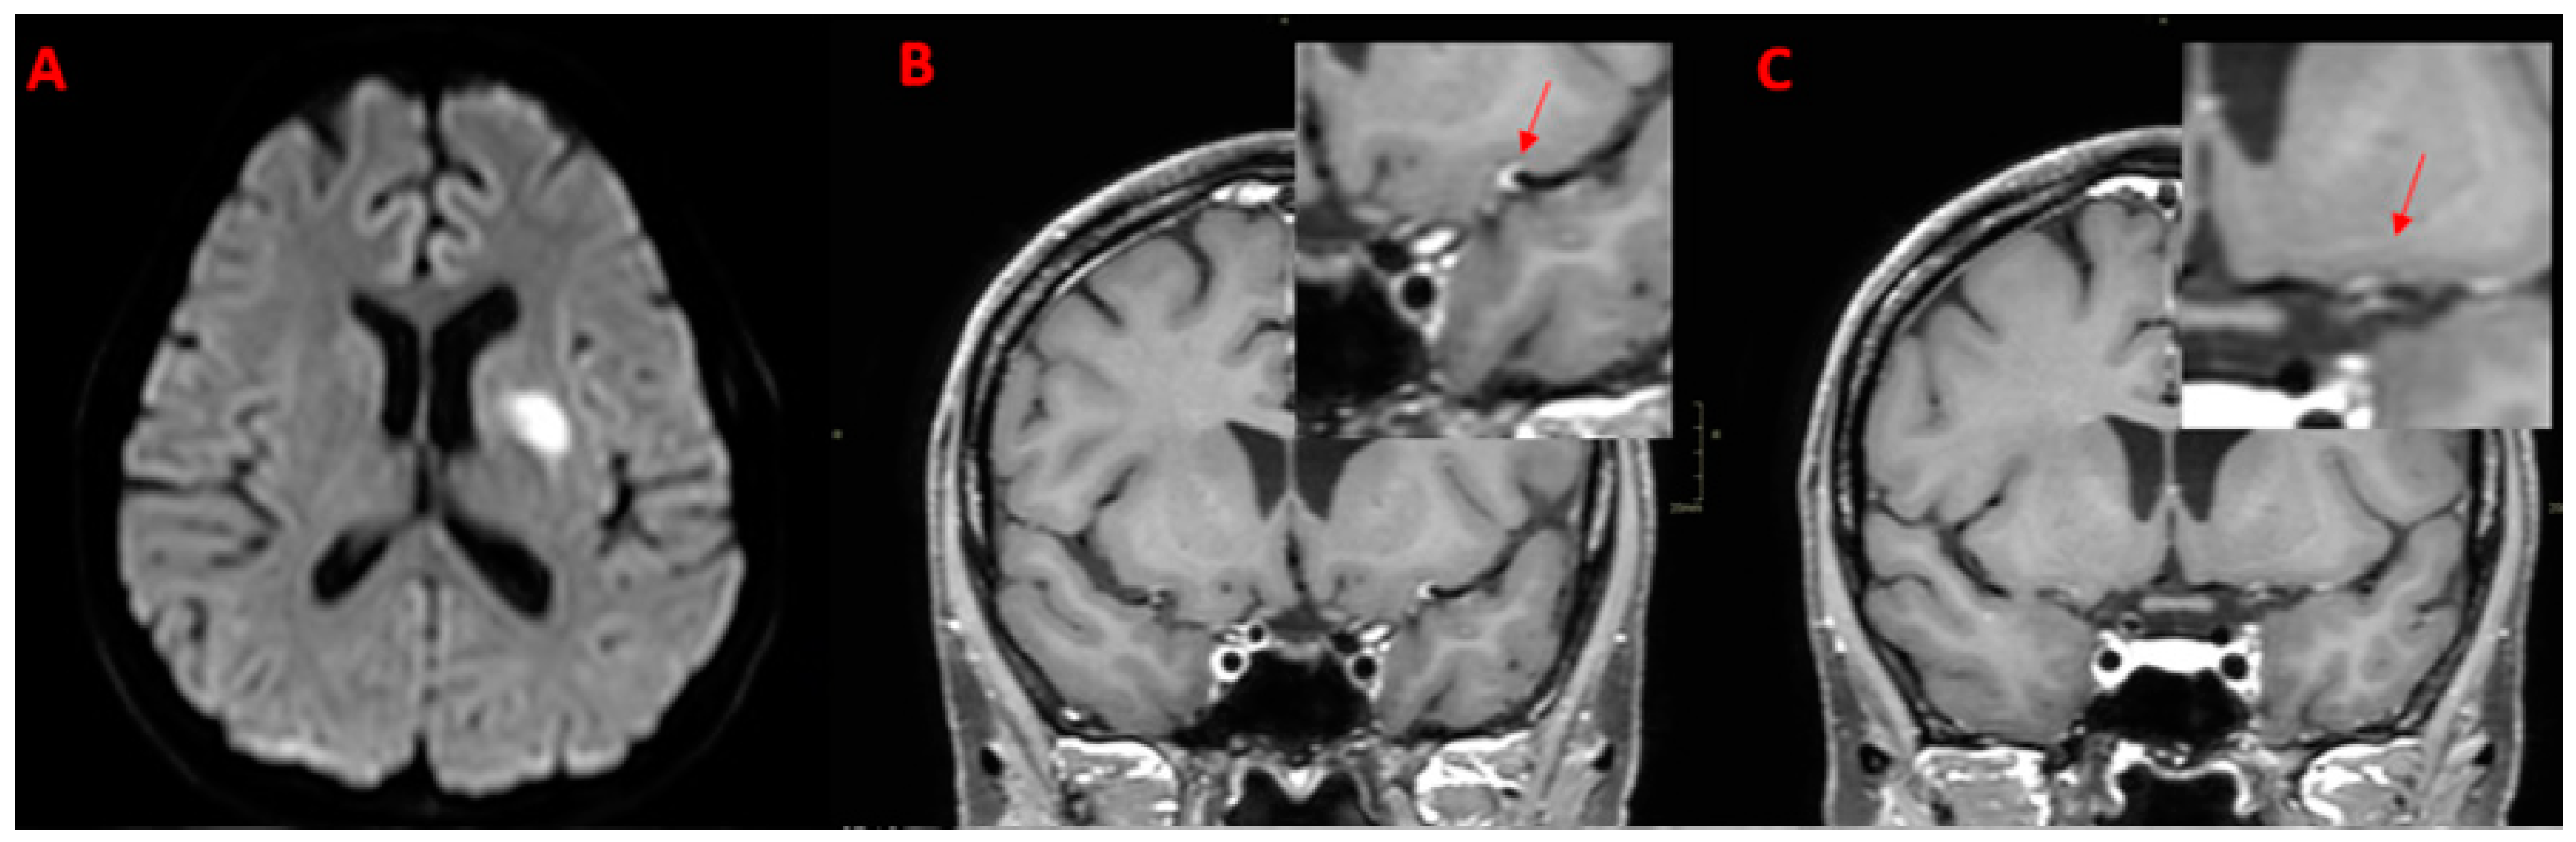

| 49Y, M | 1 | Present | Present | Multiple subcortical in MCA territories | ICA | MCA (M1) ACA (A1) | Present | Subtentorial |

| 58Y, M | 2 | Present | Present | Multiple subcortical in ACA and MCA territories and left SCA | ICA | None | Present | Supratentorial |

| SCNSV Luetic (n = 2) | 2 (100.0%) | 2 (100.0%) | 0 (0.0%) | 0 (0.0%) | 2 (100.0%) | 2 (100.0%) | 1 (50.0%) multiple: 1 (100.0%) | 1 (50.0%) | 0 (0%) | 2 (100.0%) | 0 (0%) | ACM(M1), ACA(A1), ICA |